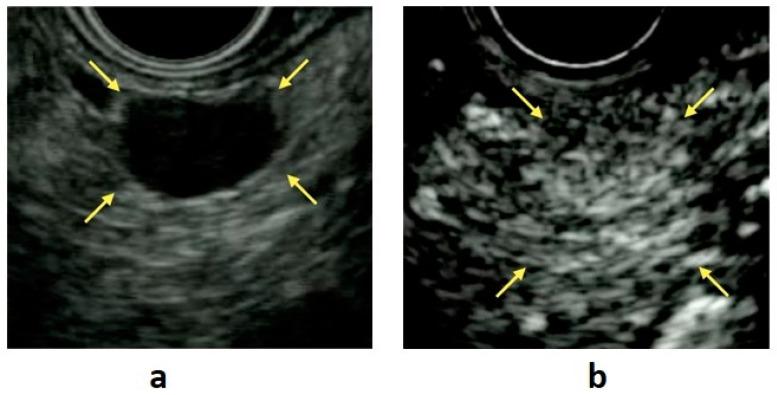

Although pancreatic neuroendocrine neoplasms (PNENs) are relatively rare tumors, their number is increasing with advances in diagnostic imaging modalities. Even small lesions that are difficult to detect using computed tomography or magnetic resonance imaging can now be detected with endoscopic ultrasound (EUS). Contrast-enhanced EUS is useful, and not only diagnosis but also malignancy detection has become possible by evaluating the vascularity of tumors. Pathological diagnosis using EUS with fine-needle aspiration (EUS-FNA) is useful when diagnostic imaging is difficult. EUS-FNA can also be used to evaluate the grade of malignancy. Pooling the data of the studies that compared the PNENs grading between EUS-FNA samples and surgical specimens showed a concordance rate of 77.5% (κ-statistic = 0.65, 95% confidence interval = 0.59-0.71, < 0.01). Stratified analysis for small tumor size (2 cm) showed that the concordance rate was 84.5% and the kappa correlation index was 0.59 (95% confidence interval = 0.43-0.74, < 0.01). The evolution of ultrasound imaging technologies such as contrast-enhanced and elastography and the artificial intelligence that analyzes them, the evolution of needles, and genetic analysis, will further develop the diagnosis and treatment of PNENs in the future.

尽管胰腺神经内分泌肿瘤(PNENs)是相对罕见的肿瘤,但随着诊断成像技术的进步,其数量正在增加。即使是使用计算机断层扫描或磁共振成像难以检测到的小病变,现在也可以通过内镜超声(EUS)检测到。对比增强EUS很有用,通过评估肿瘤的血管情况,不仅可以进行诊断,还能够检测恶性肿瘤。当诊断成像困难时,使用EUS结合细针穿刺活检(EUS-FNA)进行病理诊断很有帮助。EUS-FNA还可用于评估恶性程度。汇总比较EUS-FNA样本与手术标本中PNENs分级的研究数据,显示一致性率为77.5%(κ统计量=0.65,95%置信区间=0.59-0.71,<0.01)。对小肿瘤大小(2 cm)的分层分析显示,一致性率为84.5%,kappa相关指数为0.59(95%置信区间=0.43-0.74,<0.01)。诸如对比增强和弹性成像等超声成像技术以及对其进行分析的人工智能、穿刺针的发展以及基因分析,将在未来进一步推动PNENs的诊断和治疗。